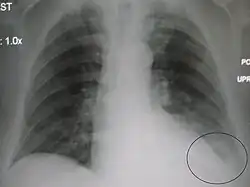

A parapneumonic effusion (circled), due to a left lower lobe pneumonia.

A parapneumonic effusion is a type of pleural effusion (accumulation of fluid in the pleural cavity) that arises as a result of a pneumonia, lung abscess, or bronchiectasis.[1] There are three types of parapneumonic effusions: uncomplicated effusions, complicated effusions, and empyema. Uncomplicated effusions generally respond well to appropriate antibiotic treatment.